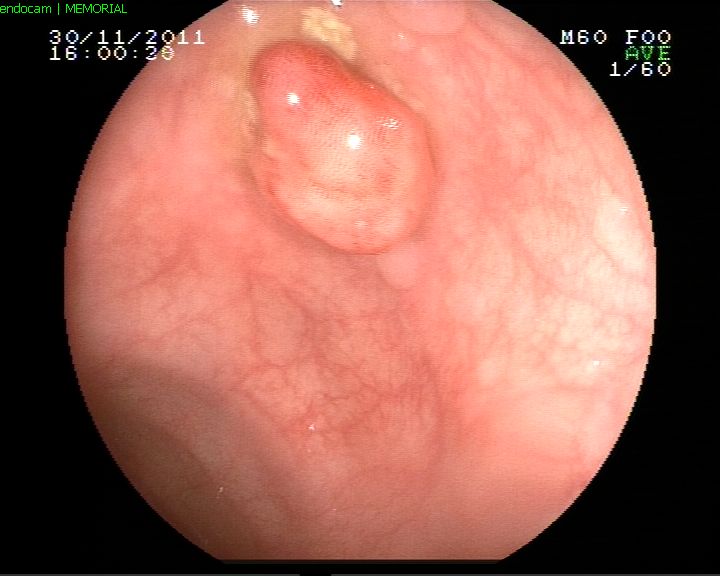

Midede polip

Kolonda polip